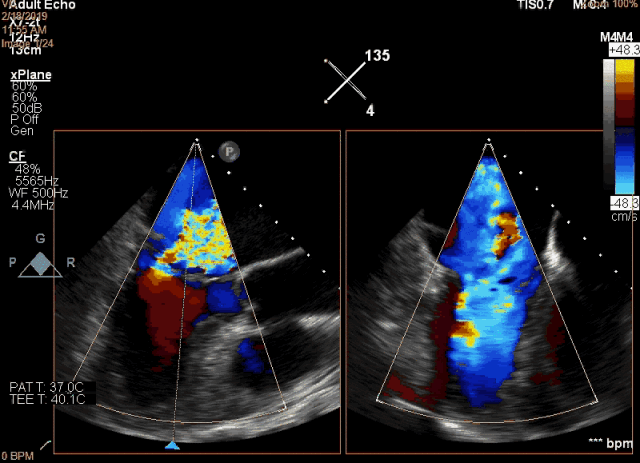

该例患者是一名78岁男性,合并症较多,基础心功能差,传统外科手术风险极高,故选择了经心尖二尖瓣夹合术(ValveClamp)。然而,术前超声评估显示,患者后叶脱垂范围极大,达23mm,P2 和P3均有脱垂,反流颈宽度达13mm。严重二尖瓣反流导致患者心功能很差,血压较低。如此广泛的脱垂,使用国外同类产品完成经导管微创二尖瓣修复也是很有挑战,甚至无法完成的。葛均波院士团队分析患者病情后,选择了使用我国自主研发的二尖瓣器械ValveClamp为患者实施经心尖二尖瓣夹合术。反复尝试数次单个夹合器夹合后,患者仍有中重度二尖瓣反流。遂采取双夹合器技术,为患者植入两个夹合器,术后即刻患者反流减少至轻度,二尖瓣跨瓣压差仅为3mmHg。该例手术是ValveClamp首例采取双夹子技术,证明了该器械行双夹子技术是安全、可行的。手术由中山医院心内科葛均波院士、周达新教授、潘文志副主任医师,心外科魏来教授,心超室的潘翠珍教授、李伟主治医师,心外麻的郭克芳教授共同完成。

图2 术前食道超声显示二尖瓣大范围脱垂及极重度反流